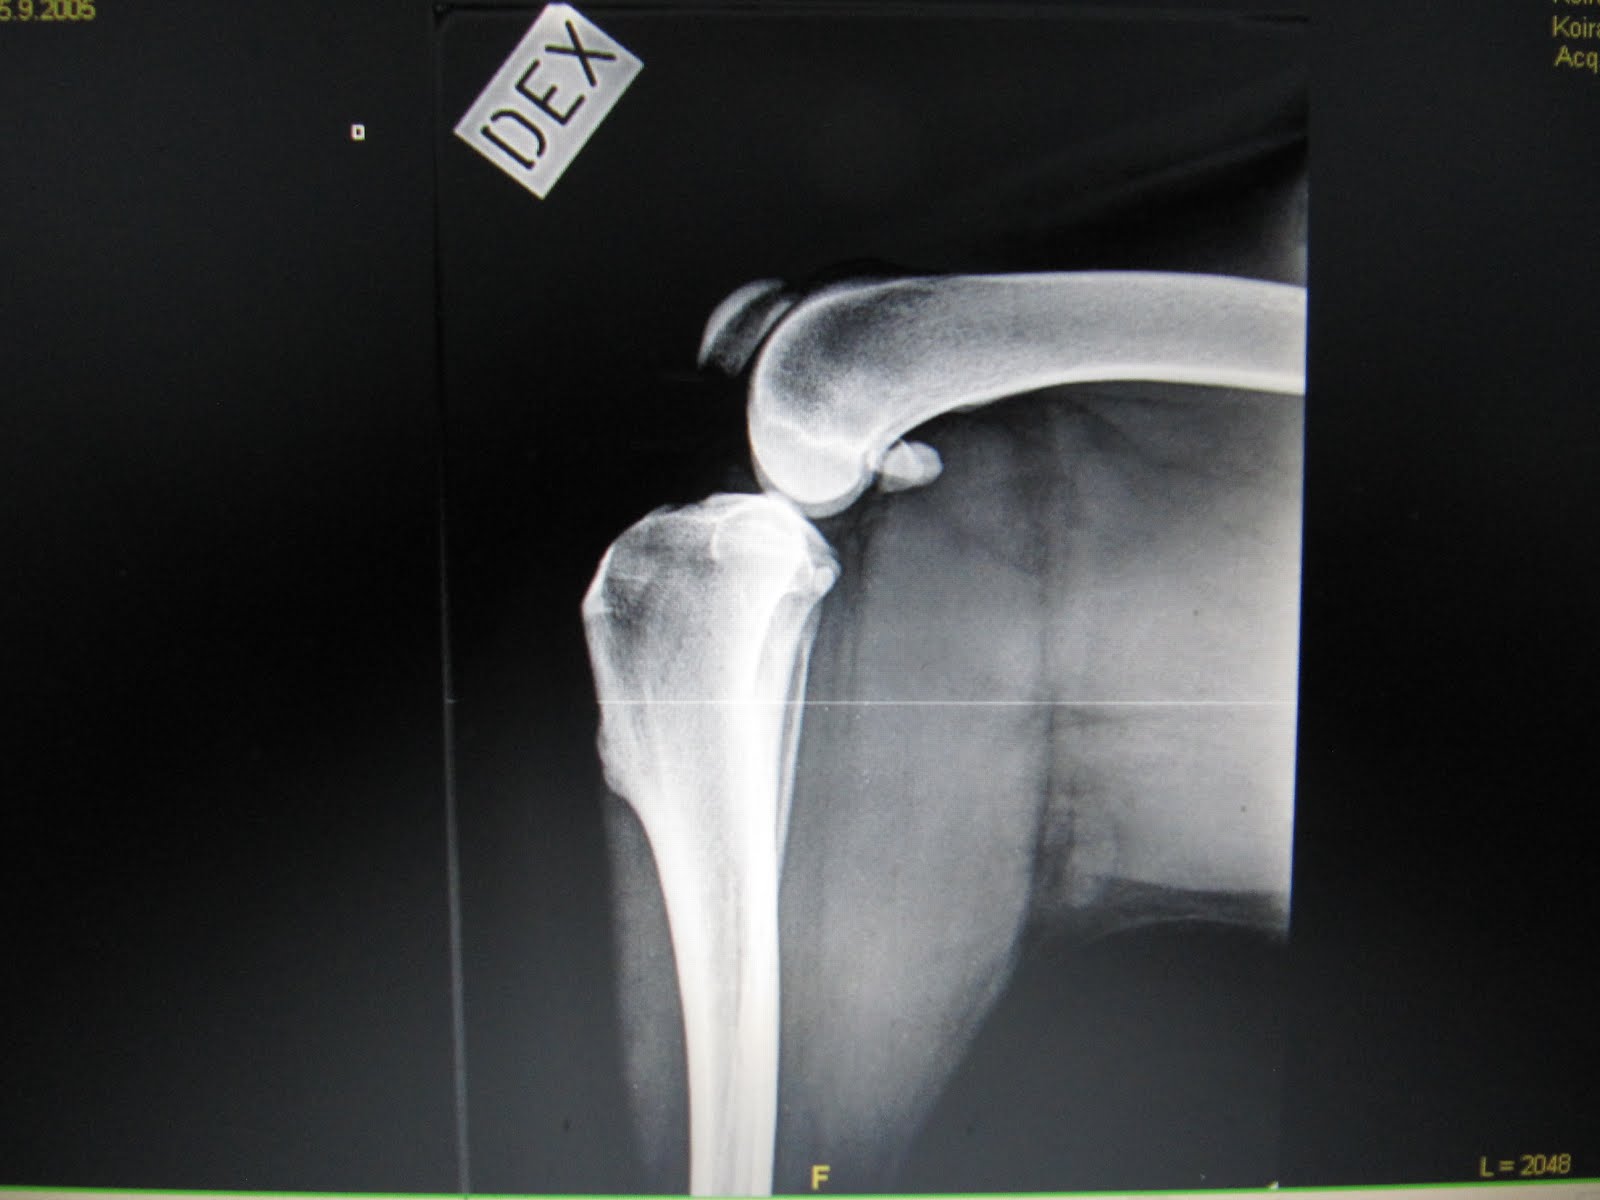

O. rauhoitettiin kuvausta varten. Vasemmassa takapolvessa lievää reisiluun luiskahtamista taaksepäin eli tukeutumispinta ei ole niin hyvä, kuin terveessä polvessa. Nivelessä lievä nivelrikko.

Polven sisänivelpinta on hiukan painunut kasaan.

Leikattu polvi. Nivelrikko näkyy pienenä rosona suoraan s-kirjaimen alapuolella.

Vertailuksi terve polvi. Tässä siis reisiluun pää oikeassa kohdassa.

Molemmat polvet samassa kuvassa. Kuvassa näkyy hyvin myös ero lihaksistossa. Sisäpuolen painuma on selvästi havaittavissa leikatussa polvessa.